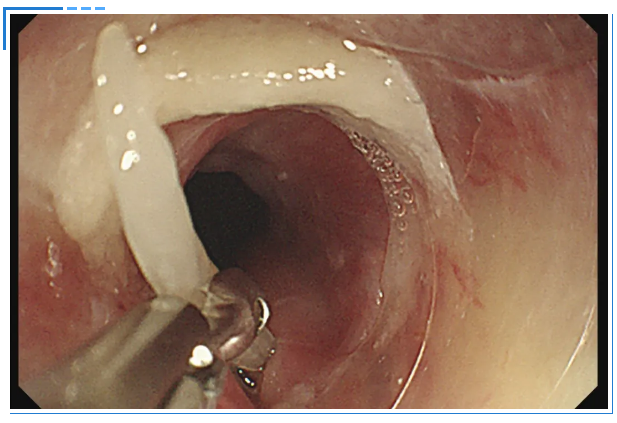

消化内镜室迅速启动取刺准备,当胃镜缓缓抵达食管入口时,清晰可见一根长约3cm的鱼刺,正斜斜嵌顿在食管入口的右侧壁,鱼刺尖端已刺入黏膜下层,周围黏膜因刺激出现明显充血水肿。更棘手的是,鱼刺恰好卡在食管入口的生理拐弯处,这个部位是食管与咽喉的衔接点,角度刁钻,内镜难以稳定固定位置。

操作医生首先尝试使用常规透明帽辅助取刺。透明帽顺利扩张开食管入口,将鱼刺完整暴露在视野中,但当异物钳从内镜操作通道伸出时,问题出现了:由于食管拐弯的角度限制,内镜操作通道与鱼刺的位置夹角过小,异物钳的活动空间被严重压缩。医生反复调整内镜角度和异物钳方向,要么视野被遮挡无法看清鱼刺,要么异物钳无法精准对准鱼刺主体,尝试了数次后,始终无法牢固夹持鱼刺,首次取刺宣告失败。